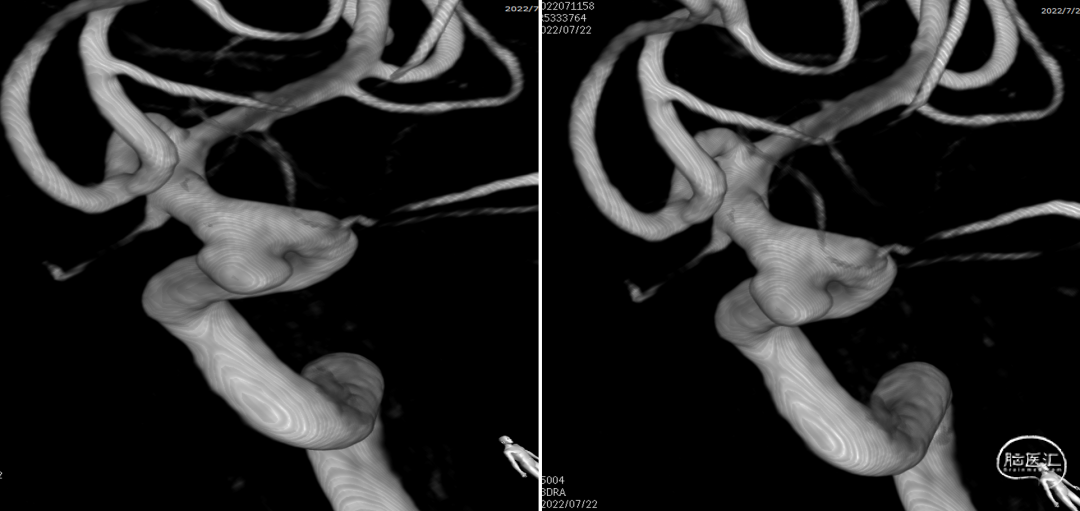

左颈内动脉3D重建图像(4.6mm*4.9mm)